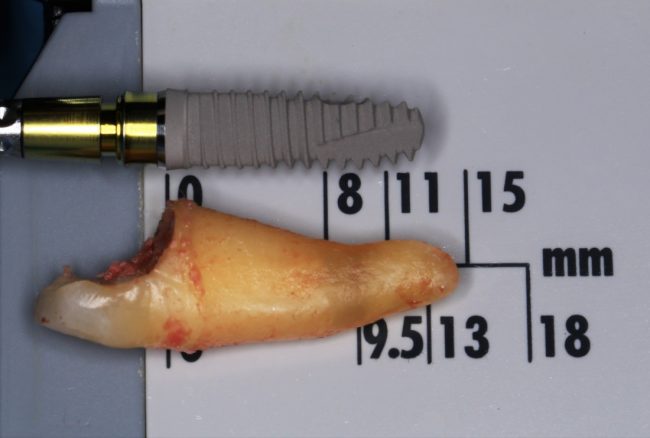

Как быть? Что делать в случае, если длина корня зуба 13 мм, а немедленно имплантировать очень-очень хочется? Простое решение — взять имплантаты длиннее, чем корень зуба (например, 15 или 18 мм). При этом, разница как в интра- так и в послеоперационном поведении данных имплантатов будет значительной — ежу понятно, что 18-миллиметровый имплантат будет стабильнее в лунке 13-миллиметрового корня зуба, чем 15-миллиметровый. Это и есть та причина, по которой производители выпускают имплантаты длиной больше 13-14 мм — в нормальных (читай, идеальных) условиях они нафиг не нужны, но когда речь идёт о немедленной имплантации, да еще и с т. н. «немедленной нагрузкой», где достижение приемлемой первичной стабильности имплантата затруднительно, нас спасают имплантаты длиной 15, 17, 18 и, в некоторых системах, даже 19 мм:

Как, например, на фотографии выше — корень удаленного зуба имеет длину 13 мм, и, если мы говорим о немедленной имплантации, для достижения достаточной первичной стабильности, нам необходим имплантат большей длины — 15 или 17 мм.

Итак, друзья, смысл подбора имплантатов по длине очень прост. В идеальных условиях не нужно на этом заморачиваться, ибо в поведении имплантов длиной, к примеру. 9 и 11 мм, разницы нет. И наоборот, очень длинные имплантаты бывают только у негров в порно, не нужно комплексовать актуальны при немедленной имплантации, когда важно достижение первичной стабильности в неидеальных условиях. Особенно, если речь идет не только об установке имплантата в лунку только что удаленного зуба, но и о фиксации временной коронки на этот имплантат: